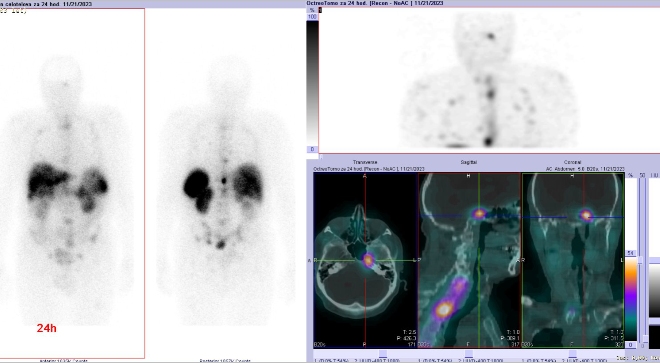

/ Obr. č. 4: Celotělová scintigrafie a SPECT/CT za 24 hod. po aplikaci OctreoScanu.

Popis: pozorujeme patologicky zvýšenou depozici radiofarmaka:

- v několika fokusech skeletu (nejkontrastněji v proc. spinosus Th10, dále v hrotu pyramidy os temporale vlevo, tělech Th3, Th6, Th8, Th12, L4, kosti kyčelní vlevo), vícečetně v žebrech oboustranně, v ldCT obraze mnohočetná smíšená převážně sklerotická ložiska

- nehomogenní kumulace v játrech, místy až s fokusy, nejnápadnější je v levém laloku ventromediálně

- v ložisku v malé pánvi pararektálně vlevo vel. cca 48x38mm

Akumulace v žlučníku, slezině, levé ledvině, močovém měchýři a střevních kličkách představuje fyziologickou distribuci.

Závěr: Mnohočetná ložiska patologicky zvýšené denzity somatostatinových receptorů, které odpovídají neuroendokrinní nádorové tkáni a generalizaci onemocnění (výrazně skelet, v ložisku v pánvi pararektálně a velmi suspektně v játrech).

U pacienta jsme prokázali mnohočetné metastázy neuroendokrinního tumoru ledviny.